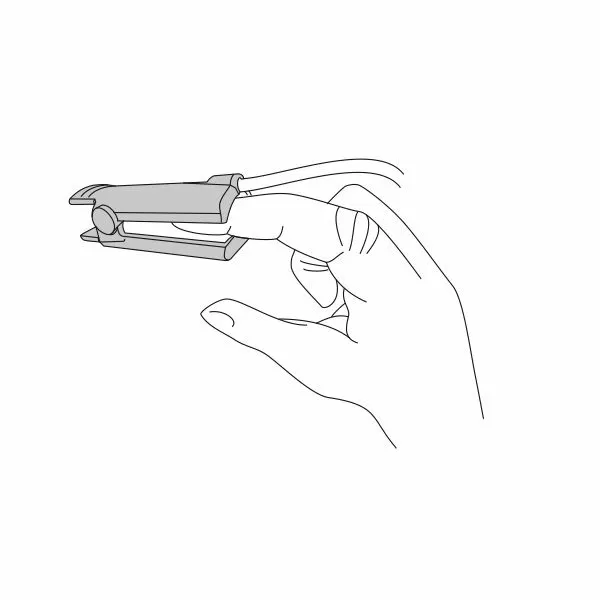

Почему может врать пульсоксиметр?

Причин, по которым пульсоксиметр может проводить измерения неверно, бывает несколько:

- у вас холодные руки. Согрейте их перед измерением;

- вы не до конца поместили палец внутрь прибора или измерению мешает длинный ноготь. Толстый слой гель-лака тоже может быть препятствием;

- вы долго находились в медицинской маске. Снимите ее, подышите глубоко и после этого делайте замер.